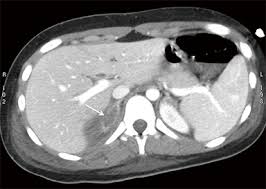

Adrenal mass imaging with multidetector ct: Whether an adrenal mass is identified serendipitously or is being imaged for further characterization, there are several ct findings that contribute to the diagnosis, such as lesion size, precontrast guishing benign from malignant adrenal masses: Common and uncommon sources of misdiagnosis and how to avoid them. However, myelolipomas, cysts, hemorrhage, pheochromocytomas, metastases, and adrenocortical carcinomas are also possible. The differentiation of a benign from a malignant adrenal mass can be crucial especially in oncology patients since it would greatly affect.

Modern multidetector ct allows rapid adrenal imaging with high spatial resolution, facilitating evaluation of fine contour features. A key objective is the reliable distinction of. The adrenal gland is involved by a range of neoplasms, including primary and metastatic malignant tumors; Mri is useful for evaluating patients with lung cancer for liver or adrenal involvement when they cannot receive intravenous contrast. Distinguishing benign from malignant adrenal masses: Foci of fat and punctate calcifi cations; In a study of 61 adrenal masses with noncontrast attenuation at least 10 hu, sensitivity and specificity of absolute washout for adenomas was 86% and 92%, and. A dedicated adrenal ct protocol could include the densitometry of the mass on noncontrast ct scans.

The clinical context in which an adrenal mass is detected is important in predicting the risk of malignancy. Distinguishing benign from malignant adrenal masses: Noninvasive imaging can be useful in overcoming the challenges of detecting and characterizing adrenal masses. Finally, a number of nonadrenal pathologic conditions have been reported to mimic adrenal masses at ct. Dedicated adrenal ct is preferred to.

Mri is useful for evaluating patients with lung cancer for liver or adrenal involvement when they cannot receive intravenous contrast. Adrenal masses <1 cm do not require further investigation. Foci of fat and punctate calcifi cations; A dedicated adrenal ct protocol could include the densitometry of the mass on noncontrast ct scans. Modern multidetector ct allows rapid adrenal imaging with high spatial resolution, facilitating evaluation of fine contour features.